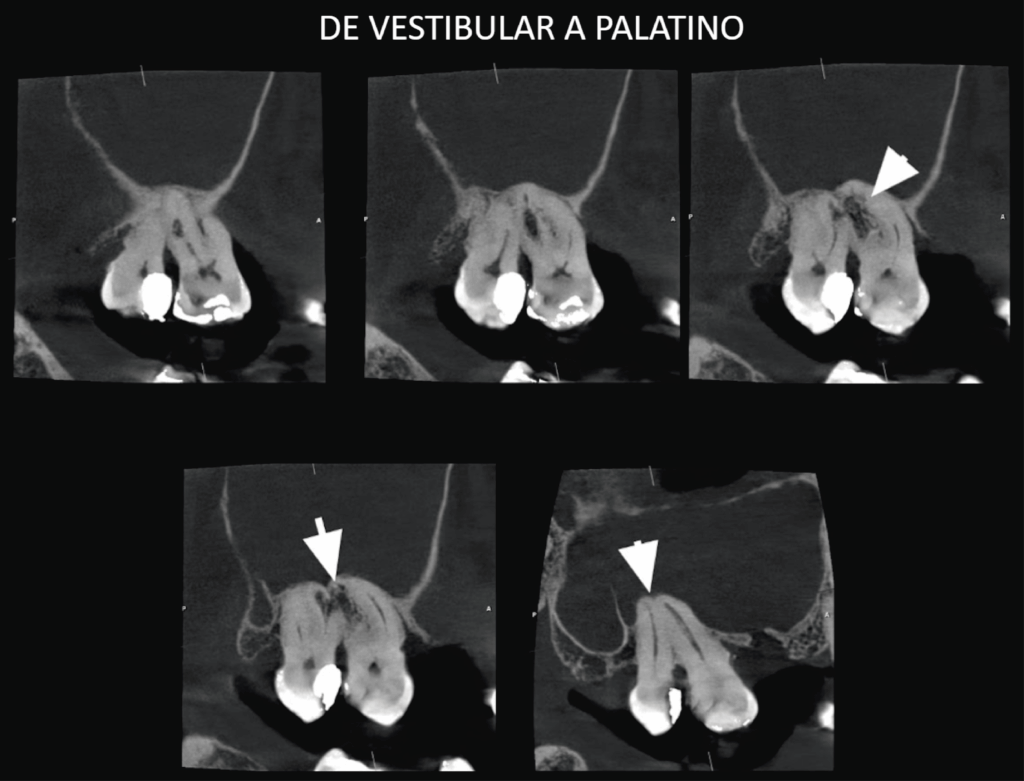

A la evaluación de la tomografía de campo reducido con un tamaño de voxel de 0.75 mm se pudo observar el seno maxilar derecho con presencia de contenido isodenso compatible con sinusitis de origen no odontogénico. Asimismo, se evidencio una reabsorción radicular externa por aposición que compromete la raíz mesiovestibular de la pieza 18 y la raíz distovestibular de la pieza 17 y que se extendía hasta conducto pulpar (visto en cortes tangenciales y axiales) y finalmente se observó hipercementosis de ambas piezas y ausencia del espacio para el ligamento periodontal perirradicular a predominio de zona interproximal de las raíces palatinas compatible con concrescencia.

CORTES TRANSAXIALES